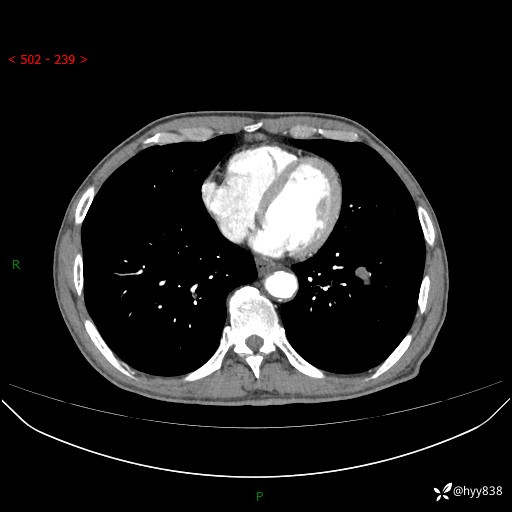

增强动脉期+静脉期

各期CT值:38Hu 52hu 55hu